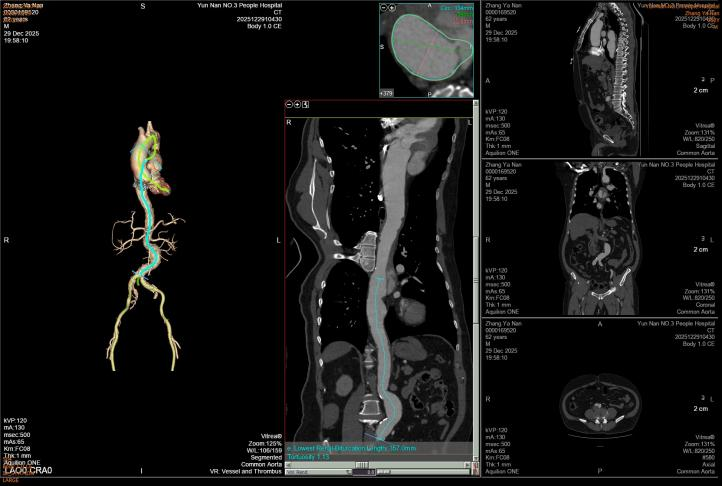

第一例患者确诊为“胸主动脉夹层合并夹层动脉瘤”,病变范围广泛。手术团队创新应用定制化打孔支架技术,术中精准定位并选择性保留重要侧支循环。该技术不仅彻底隔绝了主动脉扩张病变,更通过支架微孔有效维持了截瘫好发区域(T8-L1节段对应脊髓根动脉)的脊髓血供,显著降低了长段覆膜支架覆盖所引发的脊髓缺血及截瘫风险,为弥漫性主动脉疾病治疗提供了更安全有效的解决方案。

第一例患者术前CT